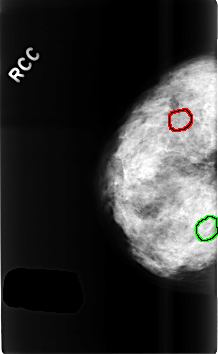

C_0498_1.RIGHT_MLO

FILE: C_0498_1.RIGHT_MLO.OVERLAY

TOTAL_ABNORMALITIES 2

ABNORMALITY 1

LESION_TYPE CALCIFICATION TYPE PUNCTATE DISTRIBUTION CLUSTERED

ASSESSMENT 3

SUBTLETY 4

PATHOLOGY BENIGN_WITHOUT_CALLBACK

TOTAL_OUTLINES 1

BOUNDARY

ABNORMALITY 2

LESION_TYPE CALCIFICATION TYPE PLEOMORPHIC DISTRIBUTION CLUSTERED

ASSESSMENT 4

PATHOLOGY BENIGN